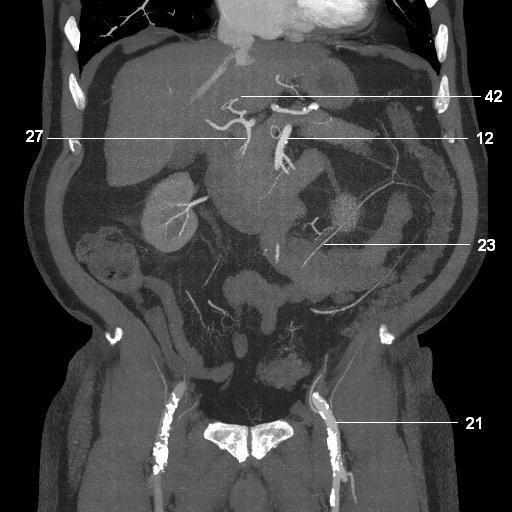

mesenteric arteriogram

12. superior mesenteric artery

21. common femoral artery

23. ascending left colic artery

27. gastroduodenal artery (GDA)

42. left hepatic artery